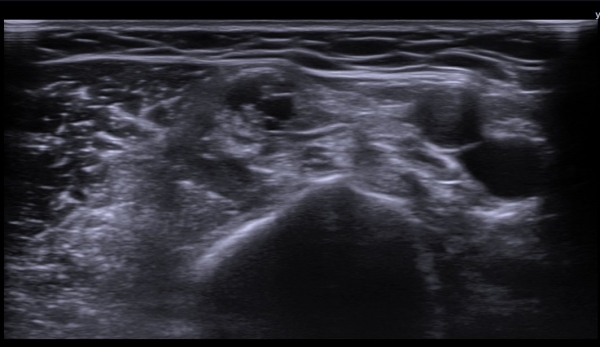

¼â°ñ¾Æ·¡¿¡¼­ »ó¿Ï½Å°æÃÑ Á¾´Ü¸é°Ë»ç¿¡¼­ »ó¿Ï½Å°æÃÑ ¿ÜÃø ²ö(lateral cord)ÀÇ Àú¿¡ÄÚ ºÎÁ¾ÀÌ

°üÂûµÈ´Ù(»çÁø 7).